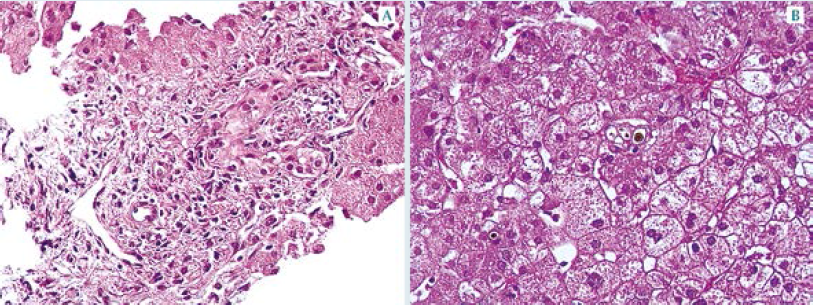

El cordón fibroso también puede estar enmascarando inflamación difusa del parénquima hepático. Nuestro paciente no reportó signos sugerentes de atresia de vías biliares. La biopsia hepática puede orientar a una obstrucción canalicular cuando están presentes marcadores típicos como: proliferación de conductos biliares, lagos y tapones que afectan todos los espacios porta; sin embargo, depende del momento en que se obtenga; por ejemplo, cuando se realiza tempranamente, antes de las 6 semanas de vida, los hallazgos distintivos pueden no estar presentes. La biopsia obtenida en el paciente de este estudio no mostró datos compatibles con obstrucción biliar. Figura 1

A nuestro paciente también se le practicó el tamiz metabólico ampliado, que permite descartar errores innatos del metabolismo de moléculas pequeñas y determina la concentración de sustancias que se acumulan en la sangre y orina, como: tirosina, fenilalanina, galactosa, fructosa, ácidos orgánicos (orina), etc.; entonces, al no detectar elevadas concentraciones de estos metabolitos, se descartan tales enfermedades. No obstante, al no establecer el diagnóstico definitivo, se estudió la posibilidad de tirosinemia, con la medición en orina y suero de succinil-acetona, pero también se descartó esta enfermedad. También se descartaron: enfermedad de Wilson (medición de ceruloplasmina y cobre en suero y orina) y deficiencia de lipasa ácida (medición enzimática). La biopsia hepática, además del diagnóstico de obstrucción, es útil para establecer el diagnóstico de enfermedades por atesoramiento (glucogenosis, Wolman, Gaucher, etc.), que también se descartaron. La biopsia de nuestro paciente sólo demostró inflamación inespecífica con datos de cirrosis. Figura 2

Un aspecto importante de comentar en este caso es la utilidad de la biopsia hepática para definir si existe o no obstrucción extra-hepática. Los criterios histológicos utilizados para distinguir entre hepatitis neonatal y atresia biliar, que representan las dos alteraciones más frecuentes de colestasis neonatal prolongada, se muestran en el cuadro 2.

Este método reporta algunos resultados falsos negativos para obstrucción. Uno de ellos implica obtener la biopsia en etapas tempranas y el otro es la obtención de tejido hepático insuficiente o inadecuado, como el que se aplicó en el presente caso. La biopsia estudiada en nuestro paciente estaba fragmentada y reveló un proceso de cirrosis, establecido por la coexistencia de grandes bandas de fibrosis. Esa fibrosis provocó fragmentación del tejido, por lo que la mayor parte de los fragmentos analizados solo mostraron la parte del lobulillo sin fibrosis. En los pacientes con cirrosis biliar en etapa avanzada pueden observase zonas de fibrosis con desaparición de los conductos interlobares y, por tanto, los criterios de obstrucción no son evidentes. Como se aprecia en la Figura 2, la fibrosis no mostró conductos evaluables, lo que impidió establecer el diagnóstico definitivo en vida.